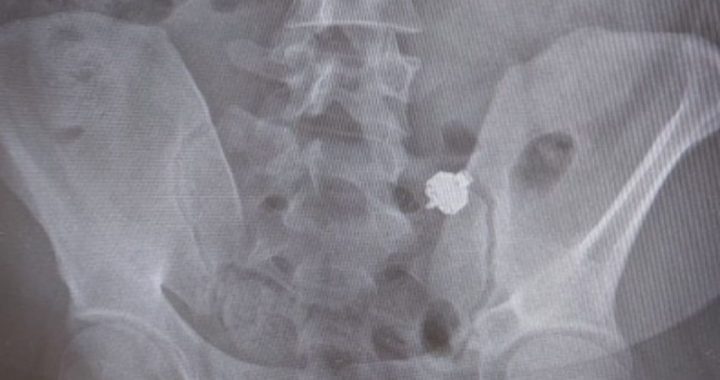

Il candidato, colto con le mani nel sacco, ha subito ingoiato il microauricolare nella speranza di nascondere le “prove”. Dopo l’accaduto è stato accompagnato al pronto soccorso e successivamente sottoposto ad una radiografia che ha evidenziato la presenza del microauricolare.